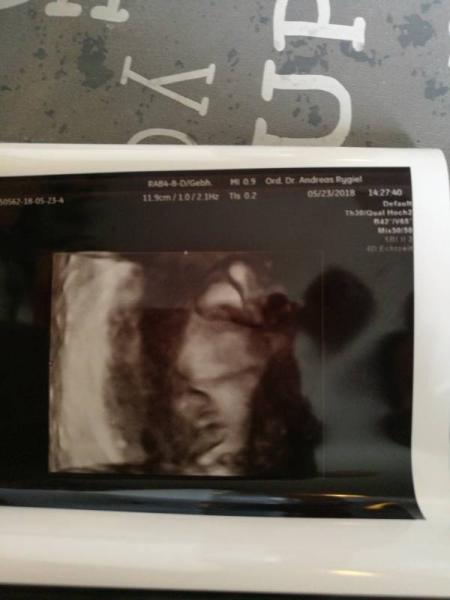

gerade vom frauenarzt heim... unser mausi ist mitn kopf verkehrt. sternenguckerin... hab damit gar keine erfahrung.. er hat gmeint, kann ne schwere lange geburt werden..oder das sie bei der steis stecken bleibt..sonst kaiserschnitt. wer hatte schon ein sternenguckerbaby???? bitte um erfahrungen... ansonsten.passt alles..2600 gramm und 31 kopfumfang mittlerweile... unten hab.ich noch ein.bild angehängt

Bild zu zurück vom Frauenarzt mit hiobsbotschaft - Forum für Juli - Mamis